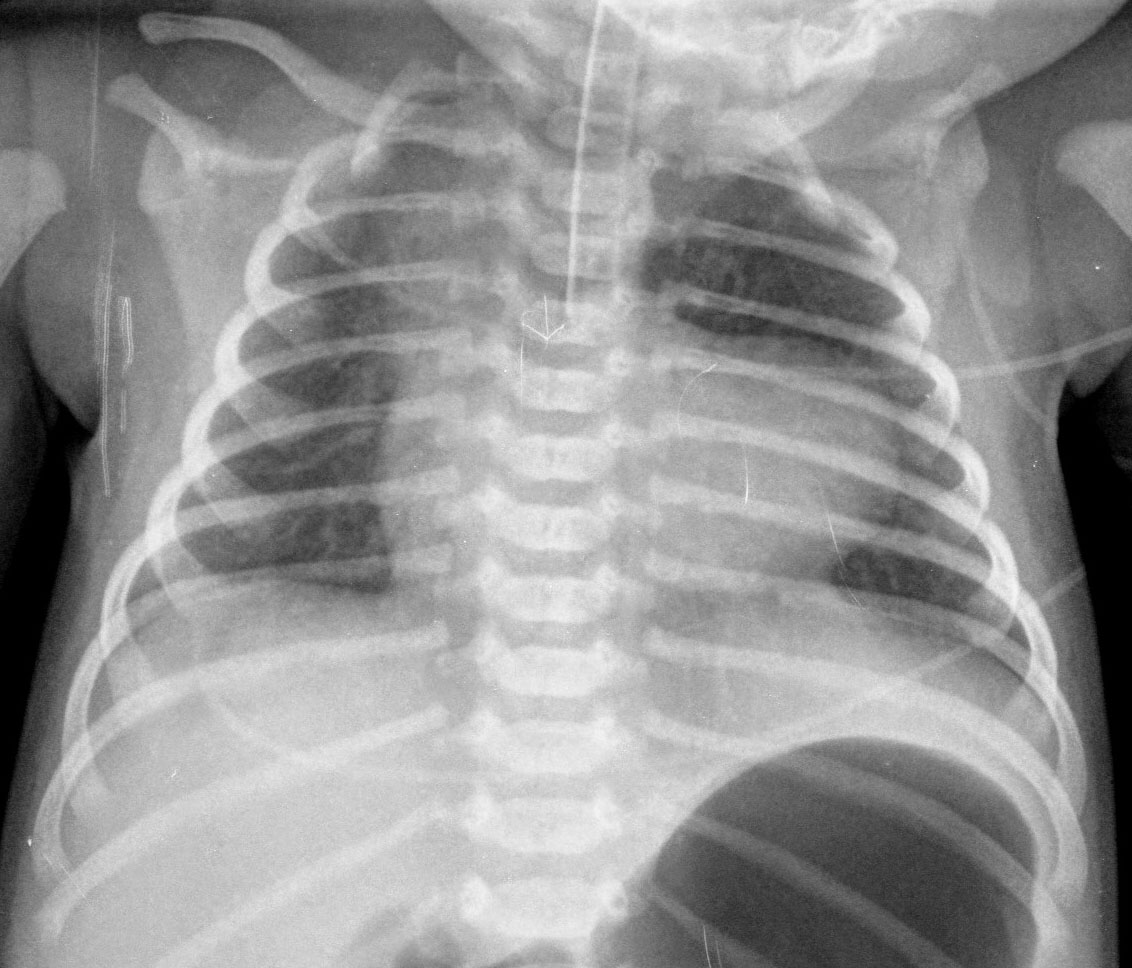

Signo de neumopericardio a tensión en la radiografía posteroanterior o anteroposterior de tórax. El neumopericardio es un hallazgo infrecuente que puede ocurrir en pacientes con traumatismo torácico. El signo del corazón pequeño consiste en una disminución del tamaño de la silueta cardiaca (como consecuencia del aumento de presión en el espacio pericárdico) y se acompaña de signos hemodinámicos de taponamiento cardíaco.

En la imagen, un caso de neumopericardio en un cadáver. Las radiodensidades puntiformes del hemitórax izquierdo corresponde a múltiples perdigones . Las flechas blancas marcan el contorno pericárdico y las rojas el cardiaco. Entre ambas, la zona radiolucente corresponde al neumopericardio.